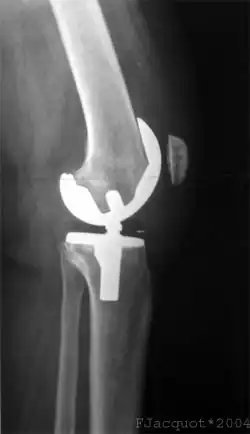

Prothèse du genou

Modèle de prothèse du genou

Une prothèse du genou est un implant articulaire interne qui remplace les surfaces articulaires défaillantes du genou, dans le but de permettre de nouveau un appui stable, la flexion et l'extension, et de récupérer un bon périmètre de marche.